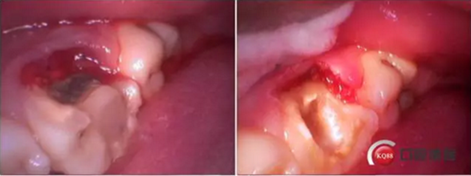

牙列完整,后牙中性關(guān)系,前牙開合,中線對齊。16合面大面積齲壞,內(nèi)褐色腐質(zhì),冷診無反應(yīng),叩痛(+-)。36合面樹脂充填,充填物在位,頰側(cè)冠折,折線位于齦緣下,冷診無反應(yīng),叩痛(+)。其他無殊。

診斷:36冠根折。

這是折線的位置,右是拔出的牙齒碎片。很明顯折裂波及遠中頰根。

先去了充填物,去腐,牙齦電切。根折根上段少量,沒有破壞根管結(jié)構(gòu)。選擇保留患牙。

牙齦切除后,根折面平整拋光,恢復(fù)頰側(cè)壁。

牙齦電刀切除,樹脂做頰側(cè)壁。